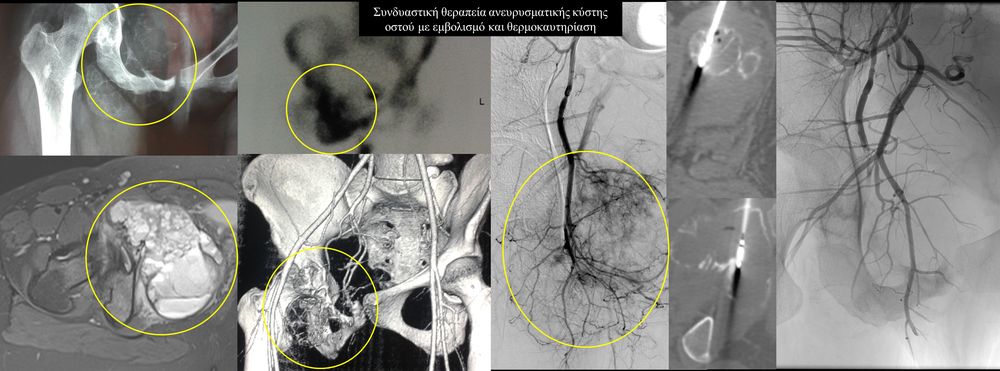

Η αντιμετώπιση του καρκινικού πόνου, εκτός από την κλασική συντηρητική φαρμακευτική θεραπεία, όταν ο πόνος επιμένει ή όταν οι παρενέργειες των φαρμακευτικών μεθόδων εξαντλούν τον ασθενή, περιλαμβάνει ελάχιστα παρεμβατικές τεχνικές με τις οποίες επιτυγχάνεται διακοπή ή καταστροφή της νευρικής οδού μεταβίβασης του πόνου. Η επεμβατική ακτινολογία διαθέτει μια πληθώρα θεραπευτικών τεχνικών που σκοπό έχουν να προσφέρουν ποιοτική βελτίωση της ζωής και των σχέσεων, τόσο των ογκολογικών ασθενών, όσο και των οικογενειών τους.